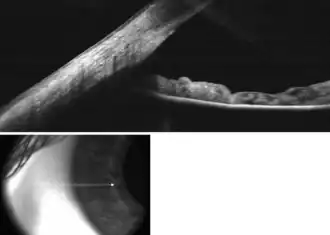

![]() Enlarged general view of the iridial angle. (When enlarged, visible with older label of 'trabecular tissue') | |

The trabecular meshwork is an area of tissue in the eye located around the base of the cornea, near the ciliary body, and is responsible for draining the aqueous humor from the eye via the anterior chamber (the chamber on the front of the eye covered by the cornea).

The meshwork is divided up into three parts, with characteristically different ultrastructures:

- Inner uveal meshwork - Closest to the anterior chamber angle, contains thin cord-like trabeculae, orientated predominantly in a radial fashion, enclosing trabeculae spaces larger than the corneoscleral meshwork.

- Corneoscleral meshwork - Contains a large amount of elastin, arranged as a series of thin, flat, perforated sheets arranged in a laminar pattern; considered the ciliary muscle tendon.[2]

- Juxtacanalicular tissue (also known as the cribriform meshwork) - Lies immediately adjacent to Schlemm's canal, composed of connective tissue ground substance full of glycoaminoglycans and glycoproteins. This thin strip of tissue is covered by a monolayer of endothelial cells.